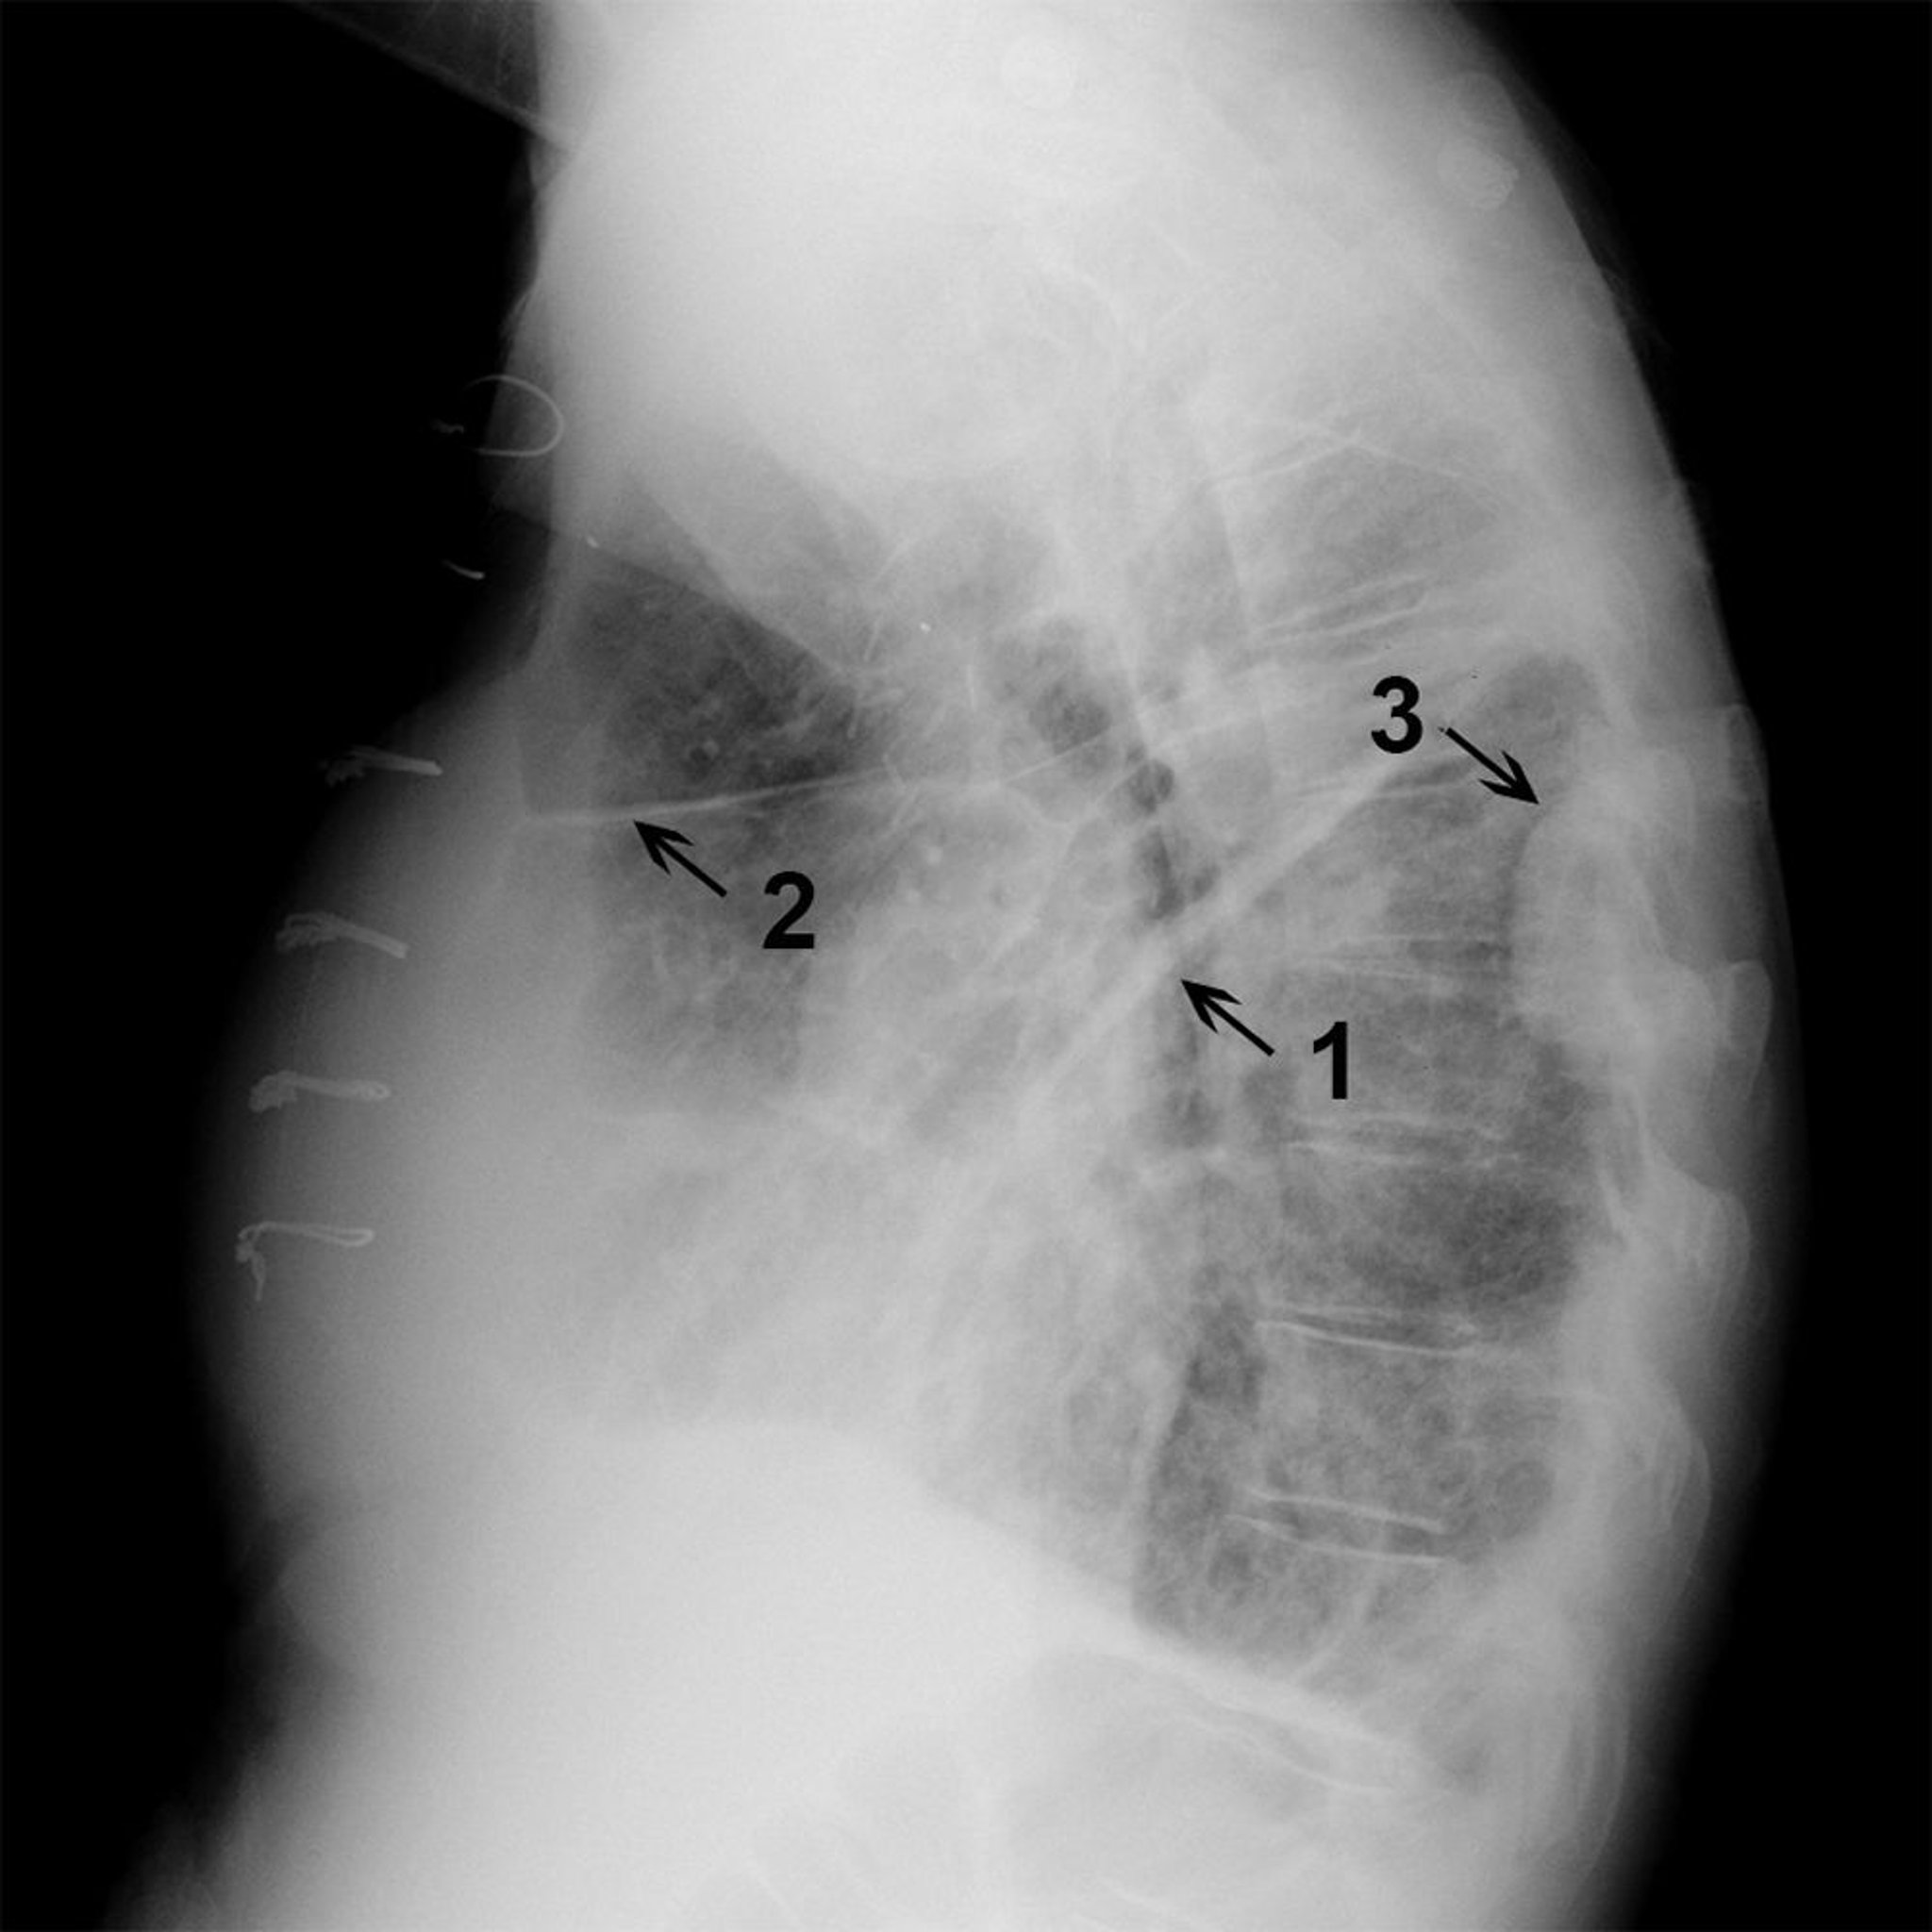

Рентгенографическое исследование грудной клетки пациента с жидкостью в горизонтальной и косой щелях правого легкого

Рентгенографическое исследование боковой части грудной клетки у пациентов с жидкостью в косой (1) и горизонтальной (2) щелях, а также с осумкованным плевральный выпотом (3), наблюдаемым вдоль задней стенки правой части грудной клетки.